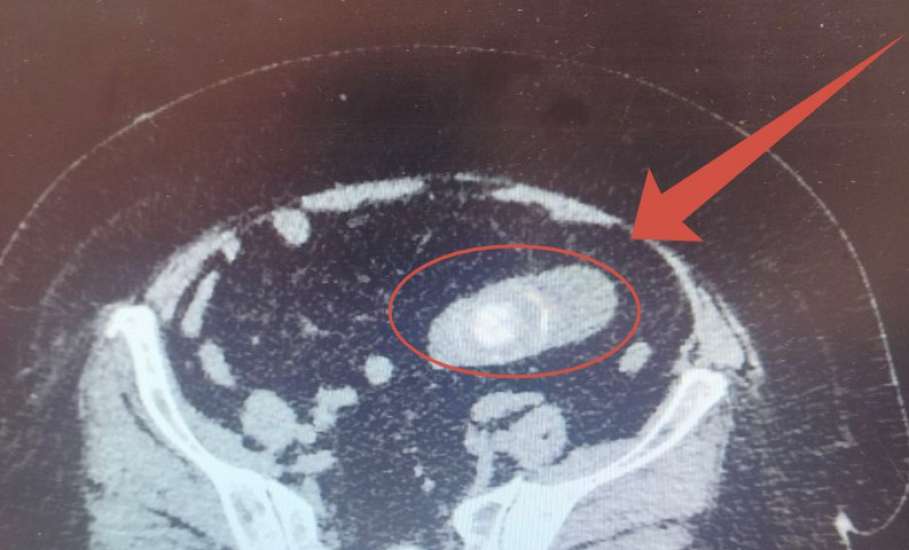

Но после операции появились сильные боли в животе и неукротимая рвота. РКТ обследование показало шокирующую картину: огромный камень в кишечнике вызвал острую кишечную непроходимость.

В ходе экстренной операции хирурги обнаружили, что камень мигрировал из желчного пузыря в кишечник через свищ. Именно он, а не почечный камень, и стал виновником тяжелого состояния.

Хирурги удалили гигантский конкремент размером 6 на 4 см и восстановили работу кишечника.